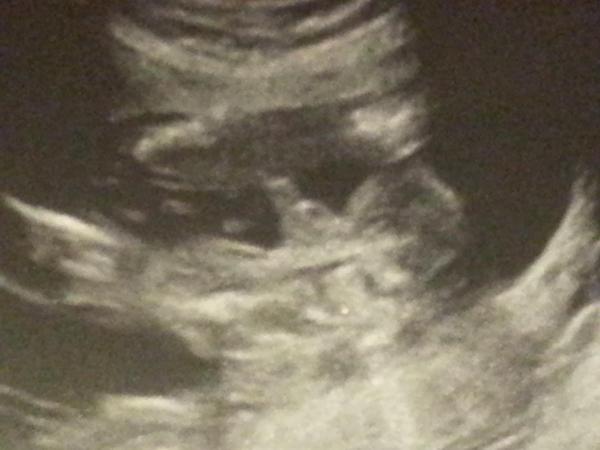

Ahoj maminky a budoucí maminky 😉 Prosím, poradila byste mi některá, co vidíte na fotce z ultrazvuku ve 20. týdnu za pohlaví? Určitě jste foteček viděly už mraky, proto vás žádám o radu...Nechci nikoho ovlivnit, proto svůj tip řeknu později 🙂 Děkuju moc!!!

Dole je zadek asi a nohy ma smerem doprava, ma je za hlavou..

@vanocni_stromecek Rekl, ze vidi holcicku, ale ze si neni jistej pak se po chvilce k.tomu vratil a rekl, zase holcicku..a dneska jsem projizdela utz video a prave co jsem zakrouzkovala, mi prislo jak pindik :D, ale zase kdyz to tes vidim, tak mi to prijde moc velky..a pod tim by to mohla bejt pipi, takovy to kavovy zrnko jak popisuji.. sama nevim a jsem zvedava :D